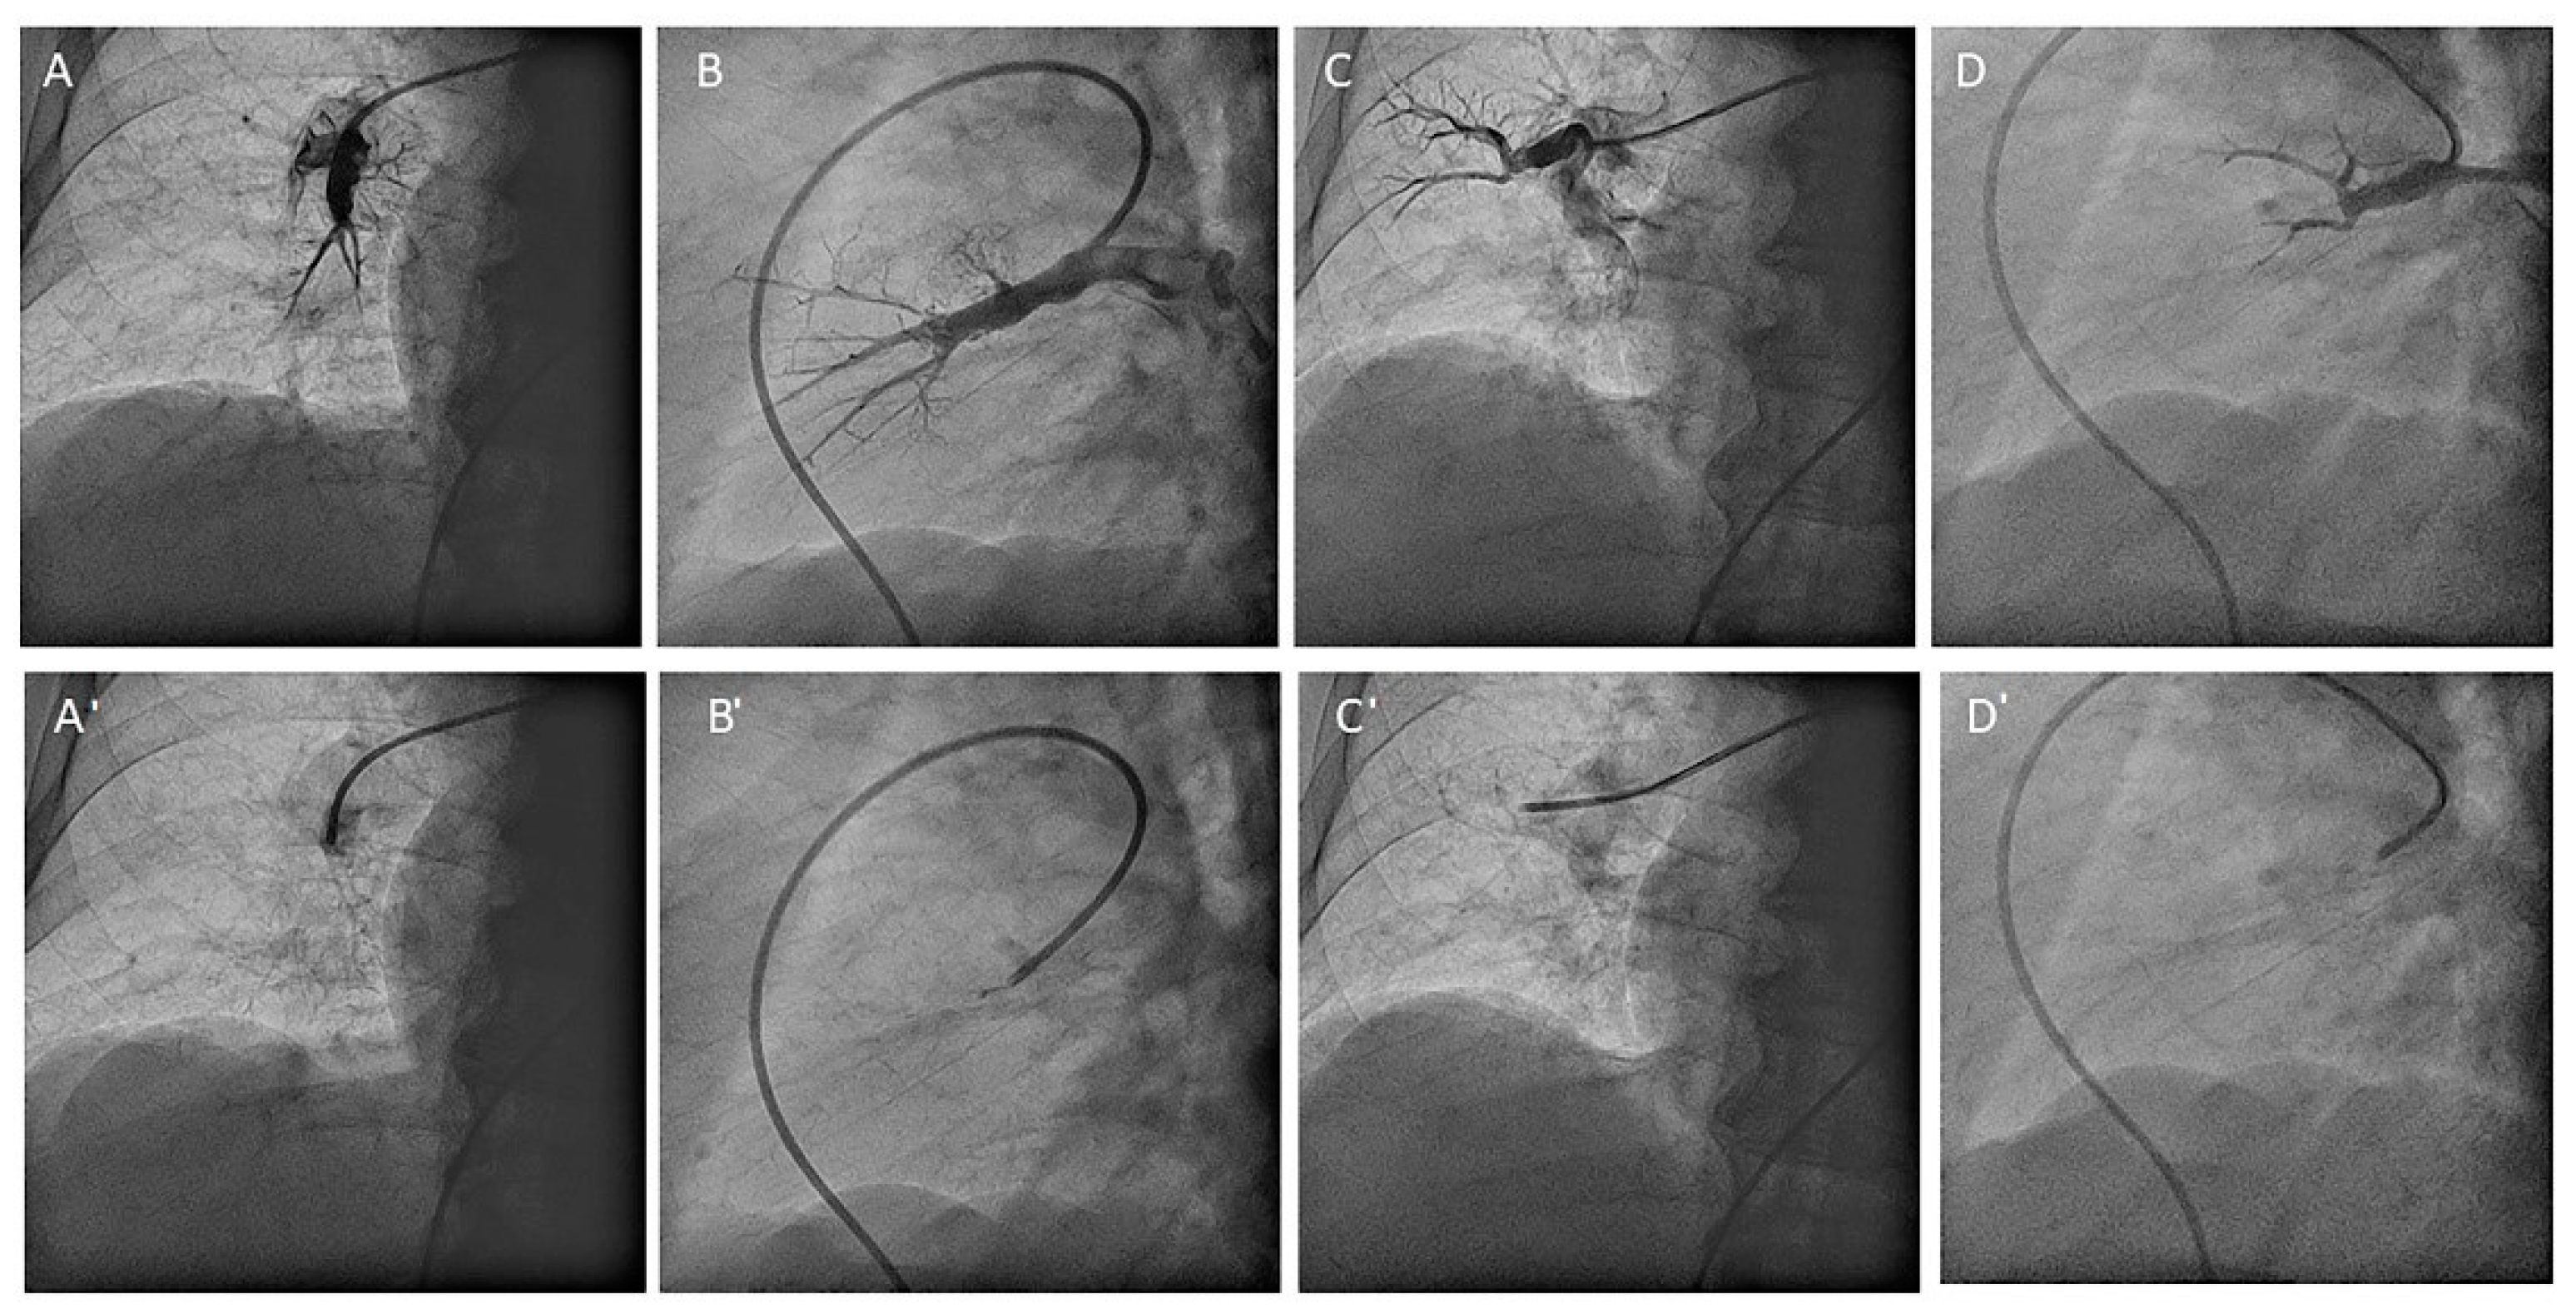

- Right upper lobe. The right upper lobar artery arises about 10 cm from the bifurcation. It is cannulated in the AP view with the tip of the MP-A2 facing upwards. The apico-posterior segmental artery (A1/2) is canalized just by advancing the MP distally once in the right upper lobe artery. The AP and lateral views display the apical (A1) and posterior branches (A2) (Figure 28). The anterior segmental artery (A3) is canalized in the lateral view, rotating the MP counterclockwise from its position in the apico-posterior artery (A1/2). With this maneuver, the tip of the catheter moves downwards, facing the sternum and engaging the anterior segmental artery (A3) (Figure 29). This branch should be filmed in lateral and cranial AP/cranial LAO view.

- Middle lobe. The middle lobe artery originates in front of the superior segmental artery of the RLL (A6), with an anterior direction, as does the lingula in the left lung (Figure 14). It is canalized with the MP, in the lateral view. The distal angulated segment of the MP should be bent, pressing against the bifurcation of the RLL, and rotated counterclockwise, with the tip of the catheter pointing towards the sternum (Figure 30). The JR 4 is also a good alternative. This artery bifurcates early in two segmental branches: lateral (A4) and medial (A5). The lateral and cranial LAO views display both branches. If these segmental branches have an independent origin in the RPA, they should be cannulated and filmed independently (Figure 31).

- Right lower lobe. The lateral projection and the MP are the best choices to canalize the two trunks of the basal pyramid and the superior segmental artery (A6). Use the AP and lateral views to assess the four segmental basal branches (Figure 32) and the lateral projection to display the superior segmental artery (A6) (Figure 16 and Figure 17).